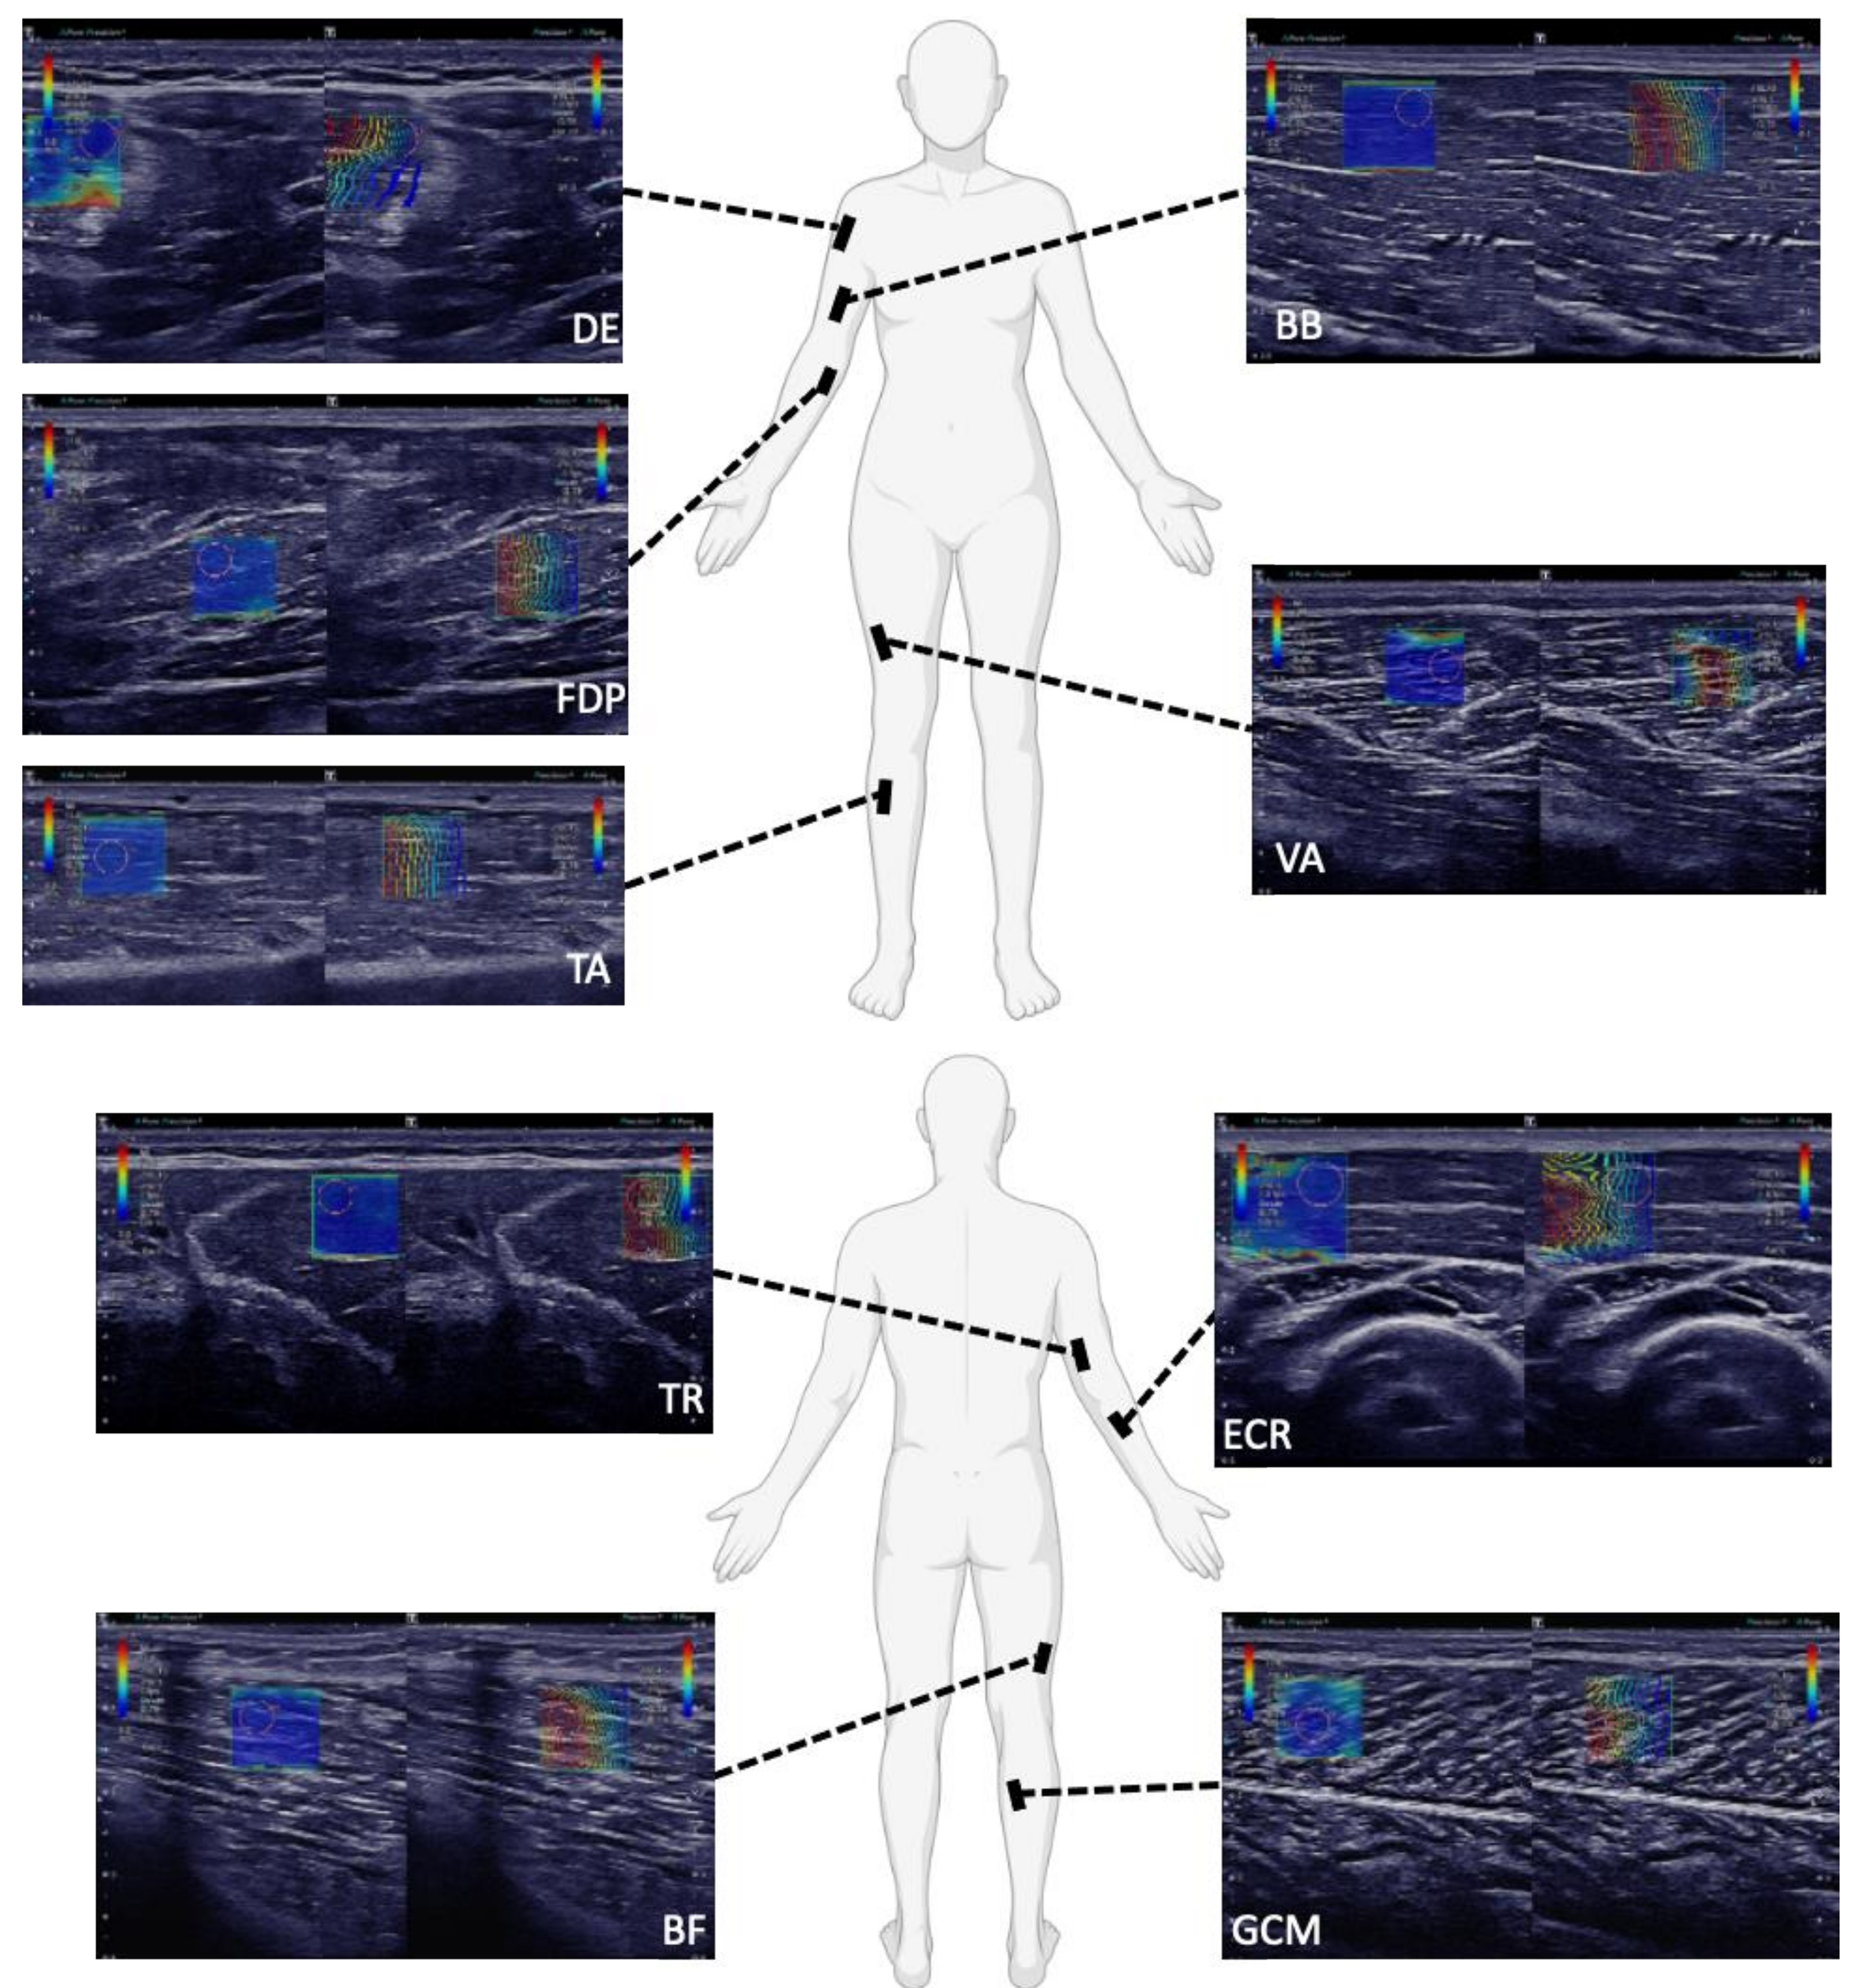

2.2. SWE Measurements and Subject Positioning

| DE | Supine, elbow resting on a pillow, arm bent at the elbow 90° | |||||||

| BB | Supine, elbow resting on a pillow, arm bent at the elbow 90° | Supine, elbow resting on a pillow, arm bent at the elbow 90° | Sitting, forearm resting, supinated underarm | Arm bent at the elbow 90° | Prone, 90° bent between legs and thighs | |||

| ECR | Supine, elbow resting on a pillow, arm bent at the elbow 90° | |||||||

| FDP | Supine, arm stretched out | |||||||

| TR | Left lateral recumbent | Arm at full extension | ||||||

| VA | Supine, legs almost completely stretched out with a small pillow under the knees | Supine, knees fully extended and feet slightly everted | Prone, lower extremity fully supported | Knee fully extended | Sitting upright, hip bent at 90° | |||

| BF | Sitting, feet flat on the floor | Prone, bent knees (90°), legs rested against a wall | ||||||

| TA | Sitting, lower leg free hanging | Supine, leg extended and heel on the examination table | Knee fully extended, ankle in neutral position | |||||

| GCM or GCL | Sitting, lower leg free hanging | Prone, feet relaxed, hanging from bed | Prone, lower extremity fully supported | Prone, hip and knee at ~ 0°, ankle at 20° plantar flexion | Supine, knee flexed and hip in external rotation | Knee bent at 90°, ankle in neutral position | Prone, 90° bent between legs and thighs | |